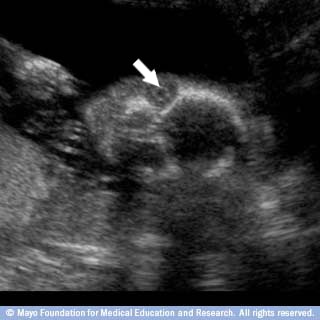

قلب الجنين

هذه الشريحة تعرض صورة للحجرات الأربع في قلب طفلك؛ إشارة مطمئنة لتطور القلب بصورة سليمة.

يبدأ جهاز القلب والأوعية الدموية بالتكون لدى الجنين في الأسبوع الخامس من الحمل، أو بعد ثلاثة أسابيع من حصول الإخصاب. ويبدأ بالنبض خلال فترة زمنية قصيرة بعد ذلك.